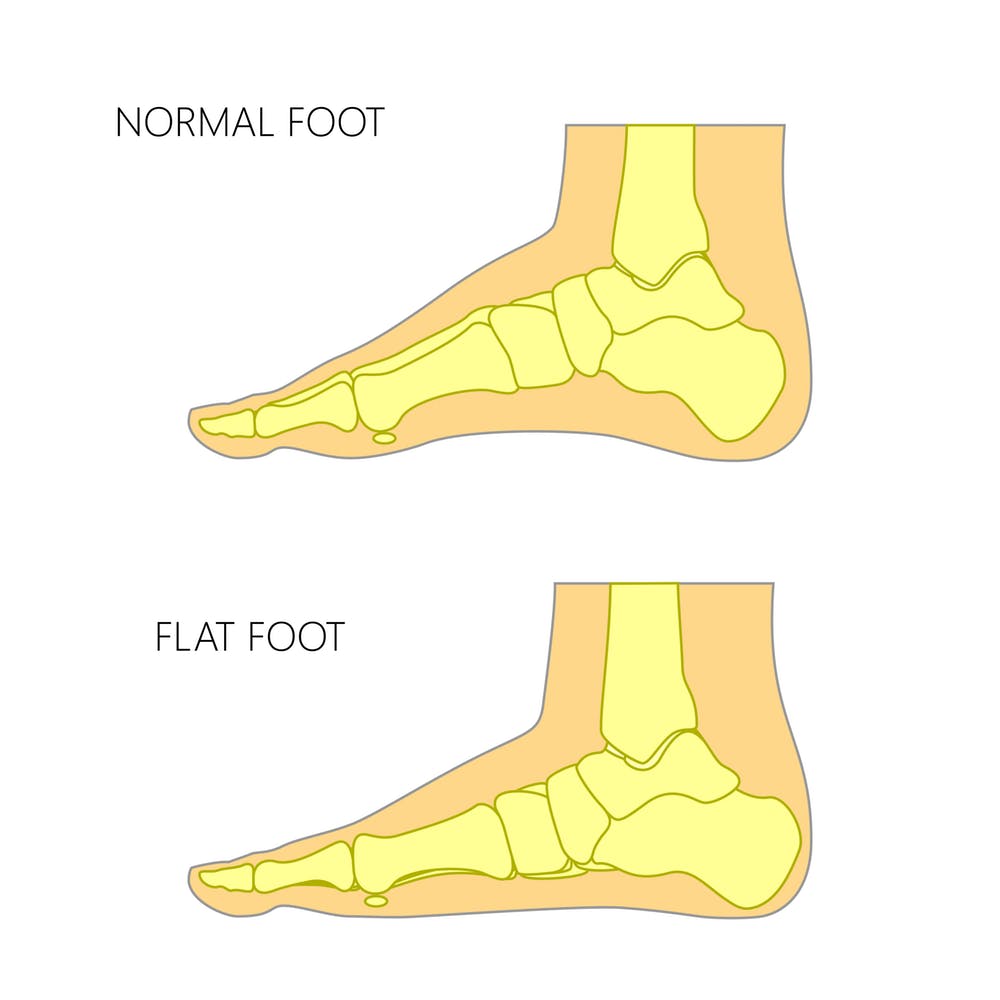

290+ อักษรรูปลิ่ม ภาพประกอบ ภาพถ่ายสต็อก รูปภาพ และภาพปลอดค่าลิขสิทธิ์ … “เท้าแบน” อยู่หรือเปล่า ถ้าเป็นอย่าปล่อยไว้ รีบแก้ไขและรักษาตัว

“เท้าแบน” อยู่หรือเปล่า ถ้าเป็นอย่าปล่อยไว้ รีบแก้ไขและรักษาตัว รีวิว RAMADA BUNION AID อุปกรณ์เฝือกอ่อนดัดนิ้วโป้งเท้าผิดรูป กระดูก …

แนะนำ แผ่นรองเท้า ป้องกันโรคกระดูกเท้าเสื่อม แผ่นรองเท้าแก้โรคเท้าแบน … กระดูก ซี่โครง 19 อันดับแรก

แนะนำ แผ่นรองเท้า ป้องกันโรคกระดูกเท้าเสื่อม แผ่นรองเท้าแก้โรคเท้าแบน … 벡터 만화 색상 캐릭터 인간의 해골 인간의 골격에 대한 스톡 벡터 아트 및 기타 이미지 – 인간의 골격, 낙서-드로잉, 만화책 …

“เท้าแบน” ภัยเงียบ ทรมานกระดูก ปวดสะโพก ไม่ใช่โรค แต่มาโดยไม่รู้ตัว … รอยเท้ามนุษย์ ไอคอน ใน iOS7 Minimal Icons

แนะนำ twilight แผ่นรองเท้า ป้องกันโรคกระดูกเท้าเสื่อม ไซส์ 35-40 แผ่น … Hallux Valgus Corrector ศัลยกรรมกระดูกเท้า Protector ปรับ Bunion Feet …